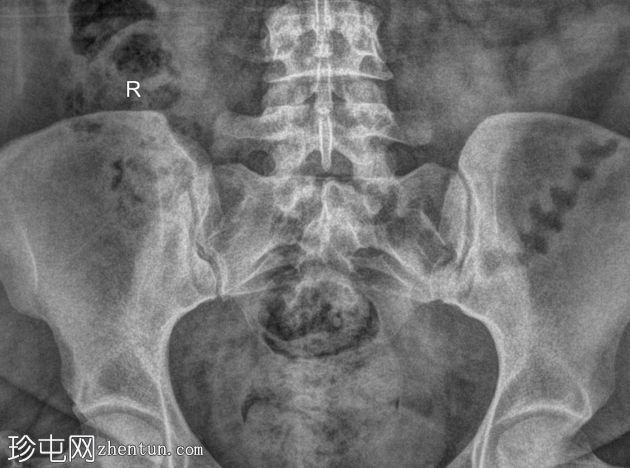

斜位

骶髂关节正位和斜位X线片显示正常。